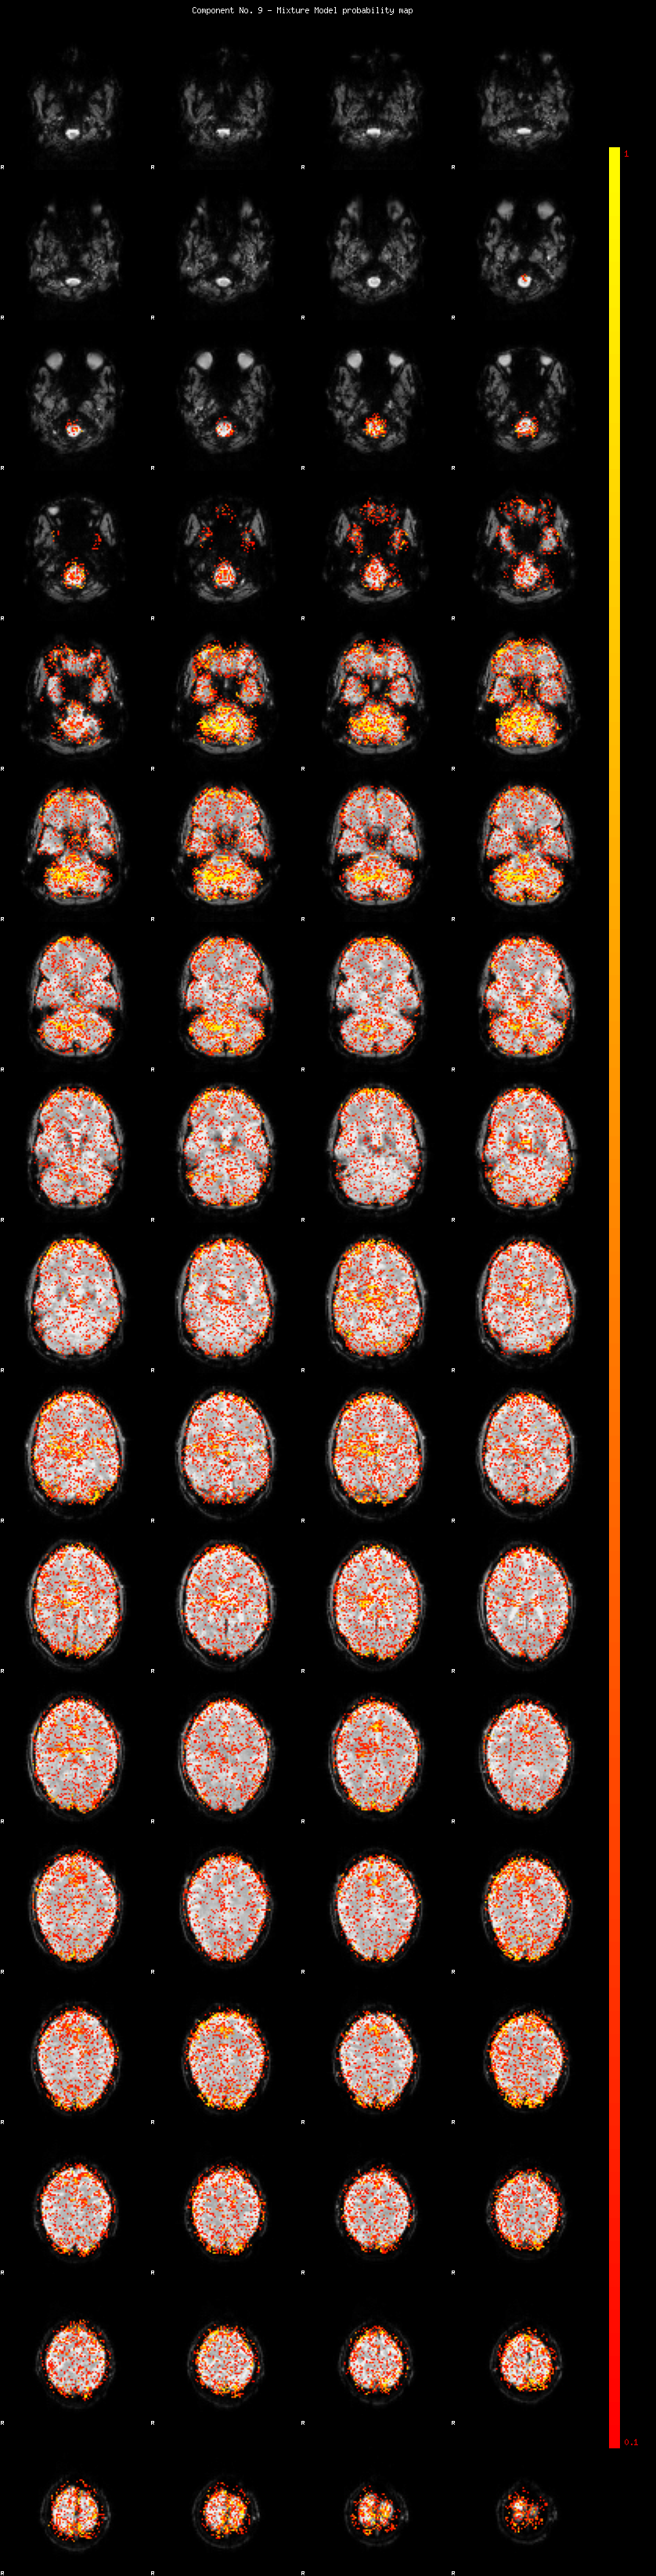

IC_9 Mixture Model fit

Means : 0.000000 2.297707 -2.273184

Vars : 1.000000 1.341158 1.289346

Prop. : 0.890360 0.057829 0.051811